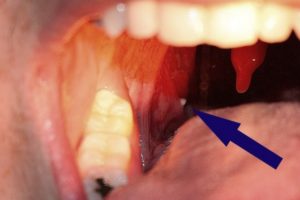

Киста после удаления (операции) в горле

Операция по удалению кисты в горле больного